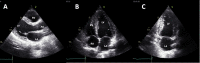

Methods: Patients with Chagas disease coming from an endemic area were selected from a large cohort (SaMi-Trop). A simplified echocardiogram with only three images was extracted from the conventional echocardiogram performed in this cohort. The images were evaluated by an observer who was blinded to the clinical and echocardiographic data, to determine the accuracy and reliability of FoCUS for cardiac assessment. The analysis constituted of 5 prespecified variables, dichotomized in absence or presence: left ventricular (LV) size and systolic function, right ventricular (RV) size and systolic function, and LV aneurysm.

Results: We included 725 patients with a mean age of 63.4 ± 12.3 years, 483 (67%) female. Abnormal electrocardiogram was observed in 81.5% of the patients. Left and right ventricular dysfunctions were found in 103 (14%) and 49 (7%) of the patients, respectively. Sensitivity, specificity, positive predictive value and negative predictive value were 84%, 94%, 70% and 97% for LV enlargement and 81%, 93%, 68% and 97% for LV systolic dysfunction, respectively, and 46%, 99%, 60% and 98% for RV dilatation, and 37%, 100%, 100% and 96% for RV dysfunction, respectively. Inter and intraobserver agreement were 61% and 87% for LV enlargement and 63% and 92% for LV dysfunction, respectively, and 50% and 49% for RV size and 46% and 79% for RV dysfunction, respectively. LV apical aneurysm was found in 45 patients (6.2%) with the lowest sensitivity of FoCUS study (11%; 95% CI 2-28%).